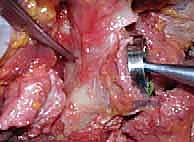

Additional Intraoperative Imaging & Surgical Steps